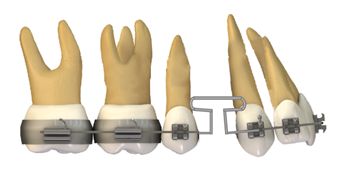

Figura 4. Tracción sector anterior con bucle.

Elaboración: Los autores.

Camuflaje con extracción de cuatro segundos premolares superiores e inferiores y minitornillos infracigomático más elásticos de clase II.

Esta técnica consiste en mejorar el perfil convexo y el sobrecrecimiento vertical con control sagital y vertical de la dentición, utilizando anclaje absoluto mediante minitornillos infracigomático (diámetro, 1,6 mm; longitud, 11 m) y también para la retracción e intrusión de los dientes anteriores, además de utilizar minitornillos a nivel mandibular para distalizar (Figura 5).

Figura 5. Cierre de espacios mini tornillos infracigomáticos.

Elaboración: Los autores.

Para un mejor efecto en cuanto al control vertical, la extracción de los segundos premolares superiores e inferiores, es recomendable para la intrusión de los molares mandibulares debido a la carga disminuida en el segmento posterior, en comparación con la extracción de los primeros premolares. Con esto no se observan diferencias significativas a nivel de los tejidos blandos en el perfil 11.

Para realizar esta técnica tanto en la arcada superior como en la inferior, deben permanecer alineadas y niveladas con la secuencia de arcos NiTi 0.012 pulgadas hasta arco de NiTi 0.018x0.025 pulgadas. Para cerrar los espacios se debe utilizar arcos de acero inoxidable con dimensiones de 0.019x 0.025 pulgadas; se aplica un resorte de NiTi desde un hook crimpable para la retracción del sector anterior con una fuerza de 100 gr. por Newton de fuerza tanto superior como inferior, para evitar la extrusión de los molares mandibulares realizando torque lingual de 25° compensatorio y para que mejore la intercuspidación, en fase final uso se implementa el uso de elásticos intermaxilares clase II. Si el paciente posee un crecimiento vertical excesivo se utiliza minitornillos para la intrusión del sector anterior 11.